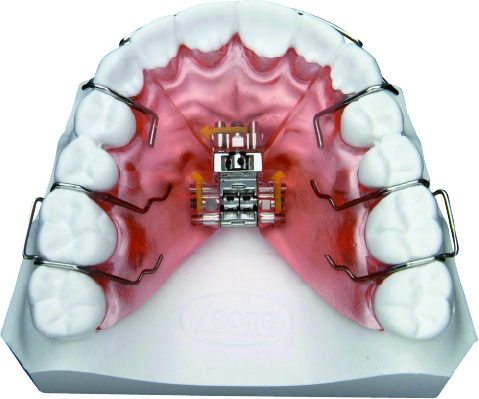

TORNILLO DE EXPANSIÓN

Los tornillos de expansión para aparatos de ortodoncia removible son el resultado de 80 años de extensas investigaciones, estudios de proyecto y millones de casos clínicos tratados.